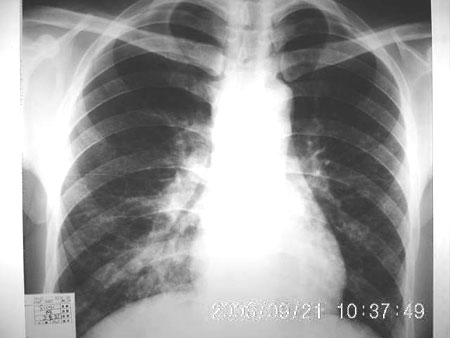

男 27岁 咳嗽一个月,治疗无效。

右肺下叶后段及右肺门附近见斑片状模糊影,密度不均,部分实变,右肺门附近见肿大淋巴结影.

两肺弥漫均匀分部粟粒壮影 右肺基底段不规则软组织密度影其内密度不均 纵隔内淋巴结钟大 请进一步右肺病灶薄层检查及补充病史后再会诊

男 27岁 咳嗽一个月,治疗无效。考虑间质性炎变,右肺下叶后基底段实质炎性结节,伴右侧肺门淋巴结肿大,不除外职业病改变,请高手指点。

右肺下叶后基底段结节样病灶,边界不规则,密度不均,右肺门团片影,肺门增大,纵隔见肿大淋巴结.结合临床首先考虑:肺结核.

图像显示:右下肺门增大,伴右下肺斑片状高密度影,密度不均;右下肺支气管管壁增厚,纵隔内淋巴结肿大。意见:支气管内膜结核、结节病。建议行纤支镜检查。

右下肺脊柱旁结节样肿块,可见毛刺,右侧肺门影增大,并见气管隆突前、主动脉窗内多发结节影。

临床无明显发热,男 27岁 咳嗽一个月,治疗无效。

考虑青年人周围型肺癌并右肺门、纵隔淋巴结转移。

右肺门影增大,纵隔内可见多个淋巴结肿大,右肺下叶内后基底段斑片状模糊影,两肺间质性改变;考虑右肺内结核并右肺门及纵隔淋巴结结核可能性大;职业病及结节病待排;肿瘤不太支持,年龄轻,无咯血,未见明显支气管狭窄,建议穿刺活检。

右肺门阴影增大,见有钙化,右肺下叶后基底段片状影,结合治疗史考虑右肺下叶结核